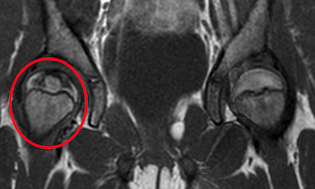

Nel forte sospetto di osteonecrosi della testa del femore, sono state eseguite radiografia, che ha mostrato un’area di osteoaddensamento e avvallamento a livello della testa femorale, e RM, che ha evidenziato la presenza di fenomeni di necrosi avascolare della testa del femore in fase evolutiva (Figura).